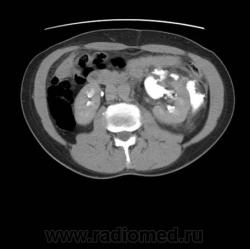

Травма. Боли в области поясницы.

Травматическое повреждение левой, по всей видимости, лоханки с разрывом и затеками контрастного препарата и мочи...